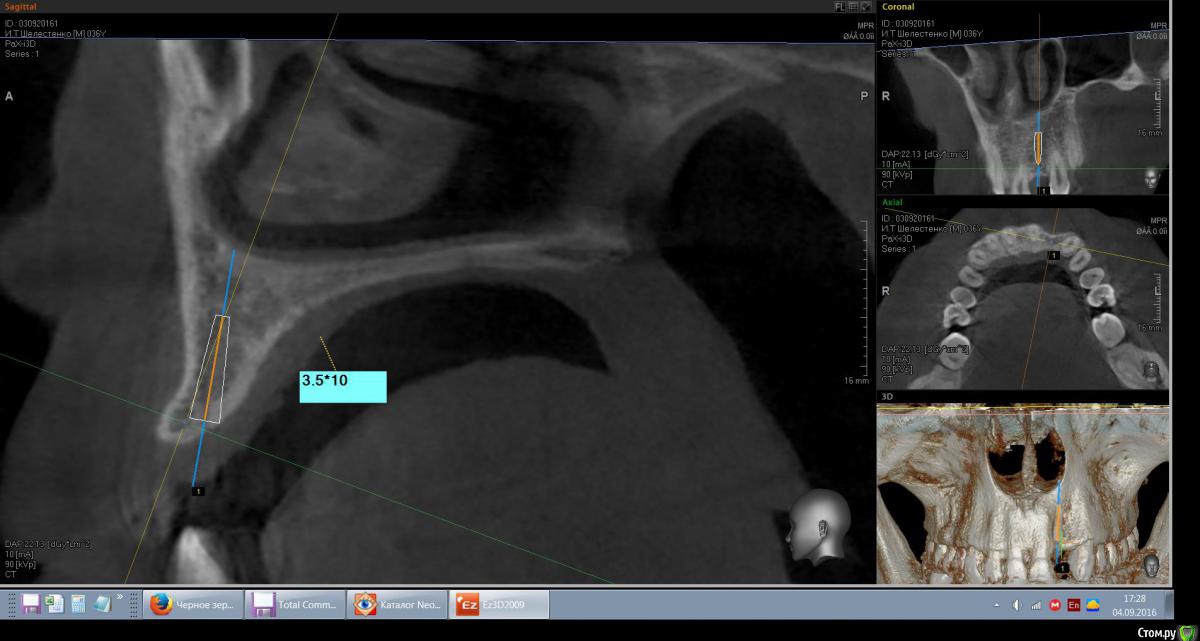

mann Опубликовано 4 сентября, 2016 Автор Поделиться Опубликовано 4 сентября, 2016 Доброе утро!Имеем такую ситуацию. Как лучше и правильно расположить имплант в данной ситуции? Ссылка на комментарий

red_butler Опубликовано 4 сентября, 2016 Поделиться Опубликовано 4 сентября, 2016 срезы выставлены не корректно 2 Ссылка на комментарий

red_butler Опубликовано 4 сентября, 2016 Поделиться Опубликовано 4 сентября, 2016 вот видите костное предложение на самом деле лучше. Только не нужно так небно ставить. Если сомневаетесь сделайте шаблон или пригласите на операцию ортопеда. И трансп добавьте. Ссылка на комментарий

mann Опубликовано 4 сентября, 2016 Автор Поделиться Опубликовано 4 сентября, 2016 И трансп добавьте. а что это?Т.е.правильным будет как на первом фото и угловой абатмент? Ссылка на комментарий

red_butler Опубликовано 4 сентября, 2016 Поделиться Опубликовано 4 сентября, 2016 а что это? трансплантат.Мне больше нравится позиция на втором снимке, только вестибулярнее и не так глубоко, и я бы ложе готовил эспандерами или чуток расщепился бы Ссылка на комментарий

kamranchick Опубликовано 4 сентября, 2016 Поделиться Опубликовано 4 сентября, 2016 а что это?Т.е.правильным будет как на первом фото и угловой абатмент?мясца с бугорка, если постарайтесь то можно даже прямой абатмент сделать. при позиционировании смотрите на нижние антагонисты Ссылка на комментарий